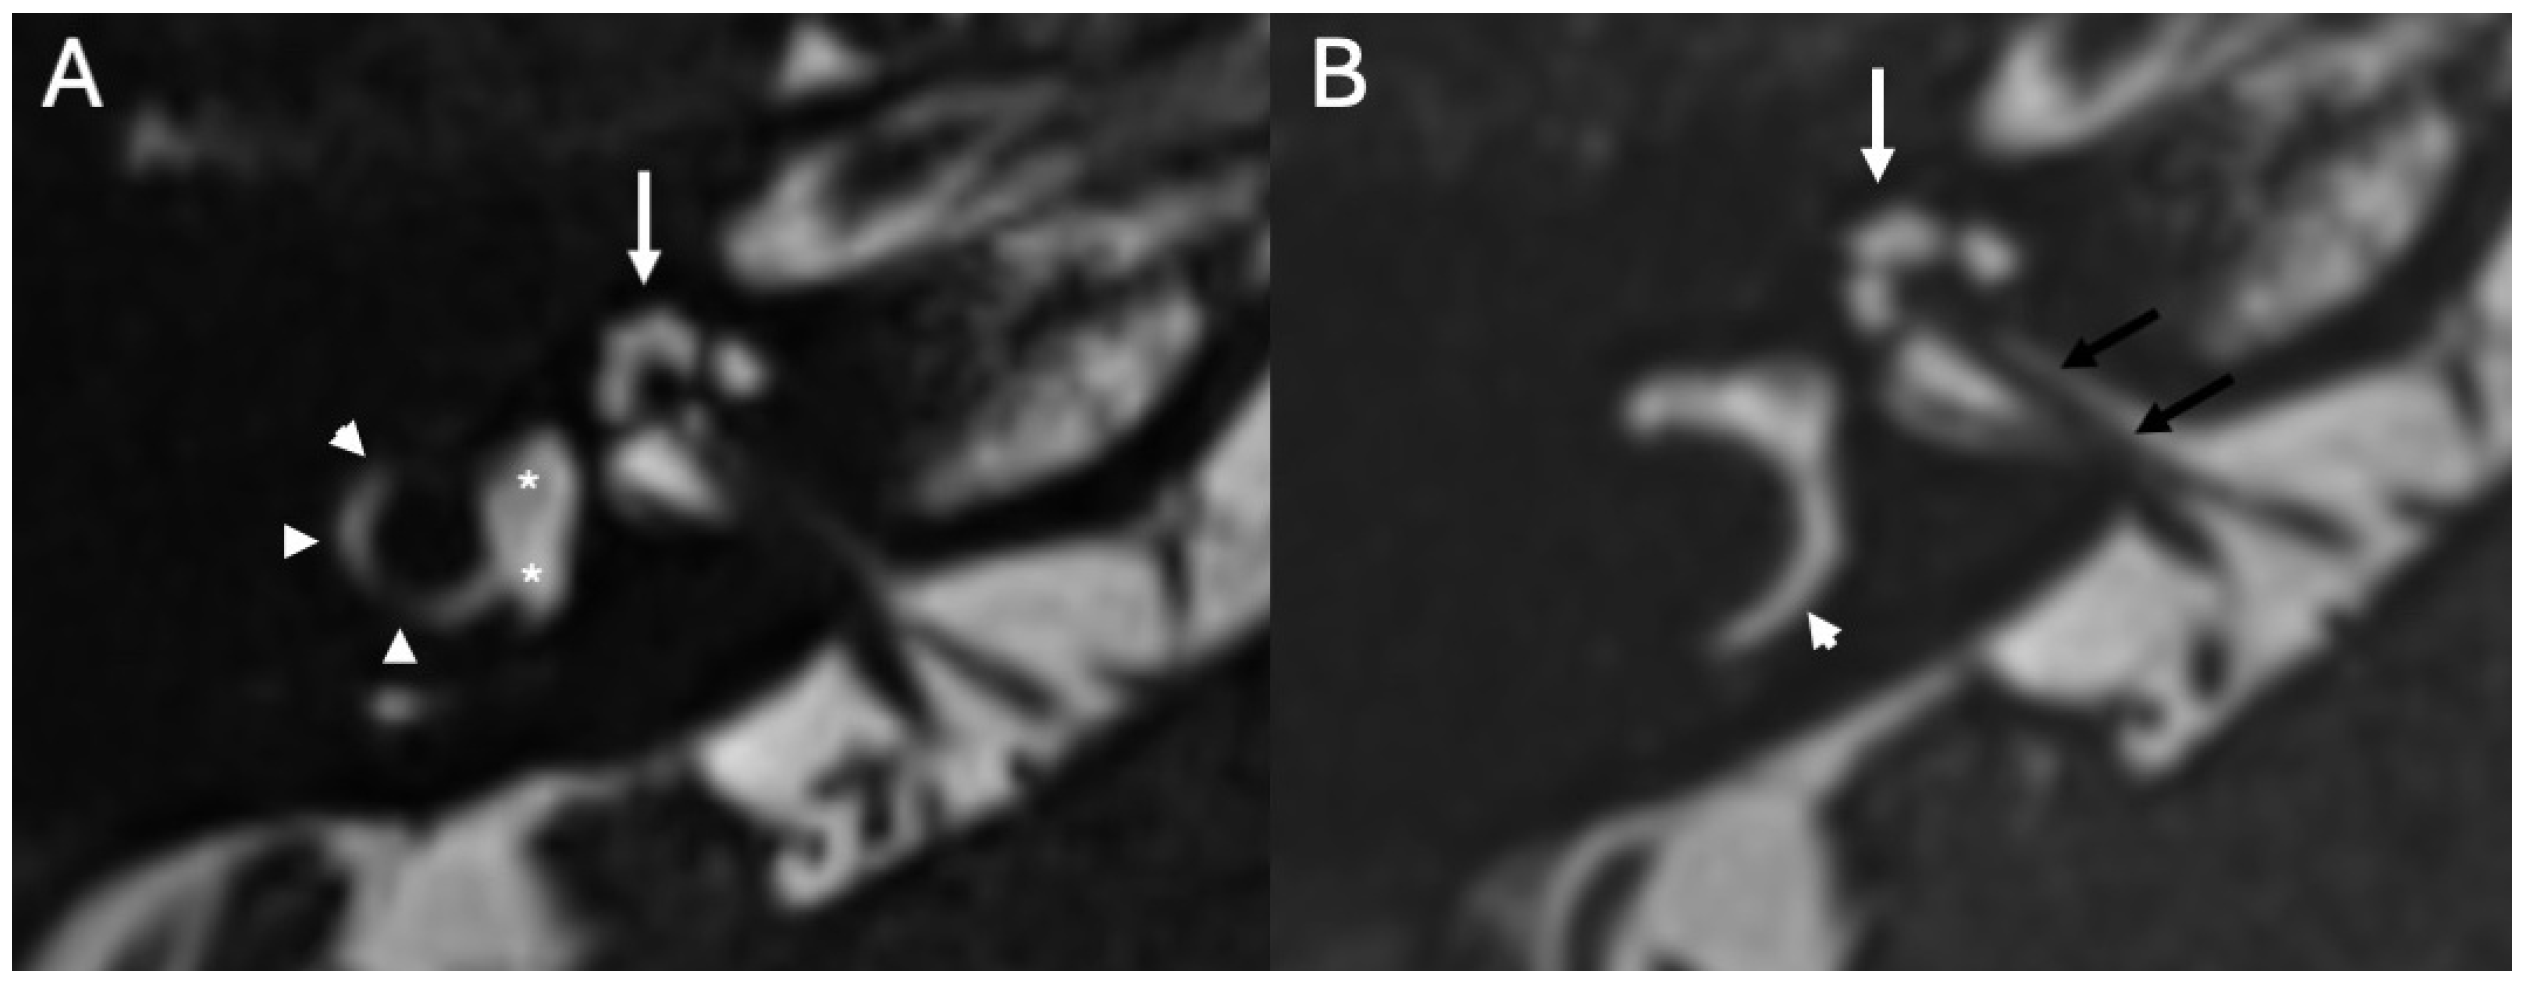

3.4. Labyrinthitis and Vestibulocochlear Neuritis

Imaging

3.5. Cochlear Hemorrhage